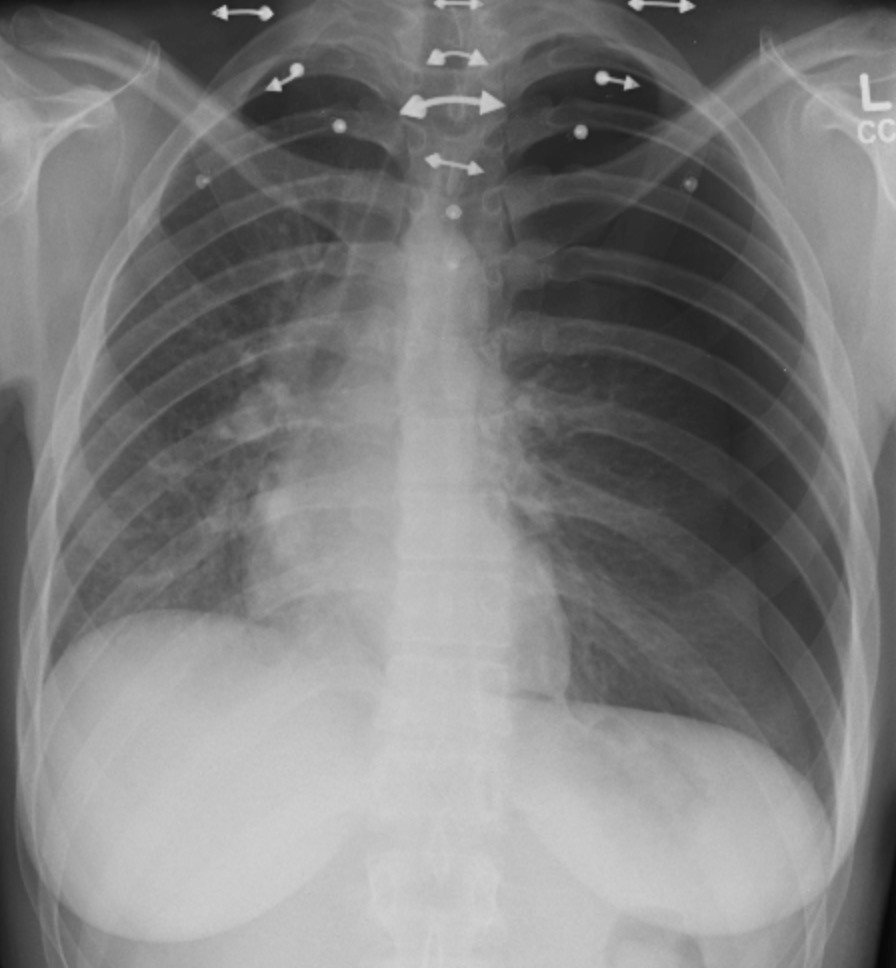

Chest X-Ray of a Pregnant Asthmatic Patient

Author: Dr. Aqsa Ali

Date Published: Mar 19, 2026

Disease Specialty: Pulmonology

Image Type:

X Ray